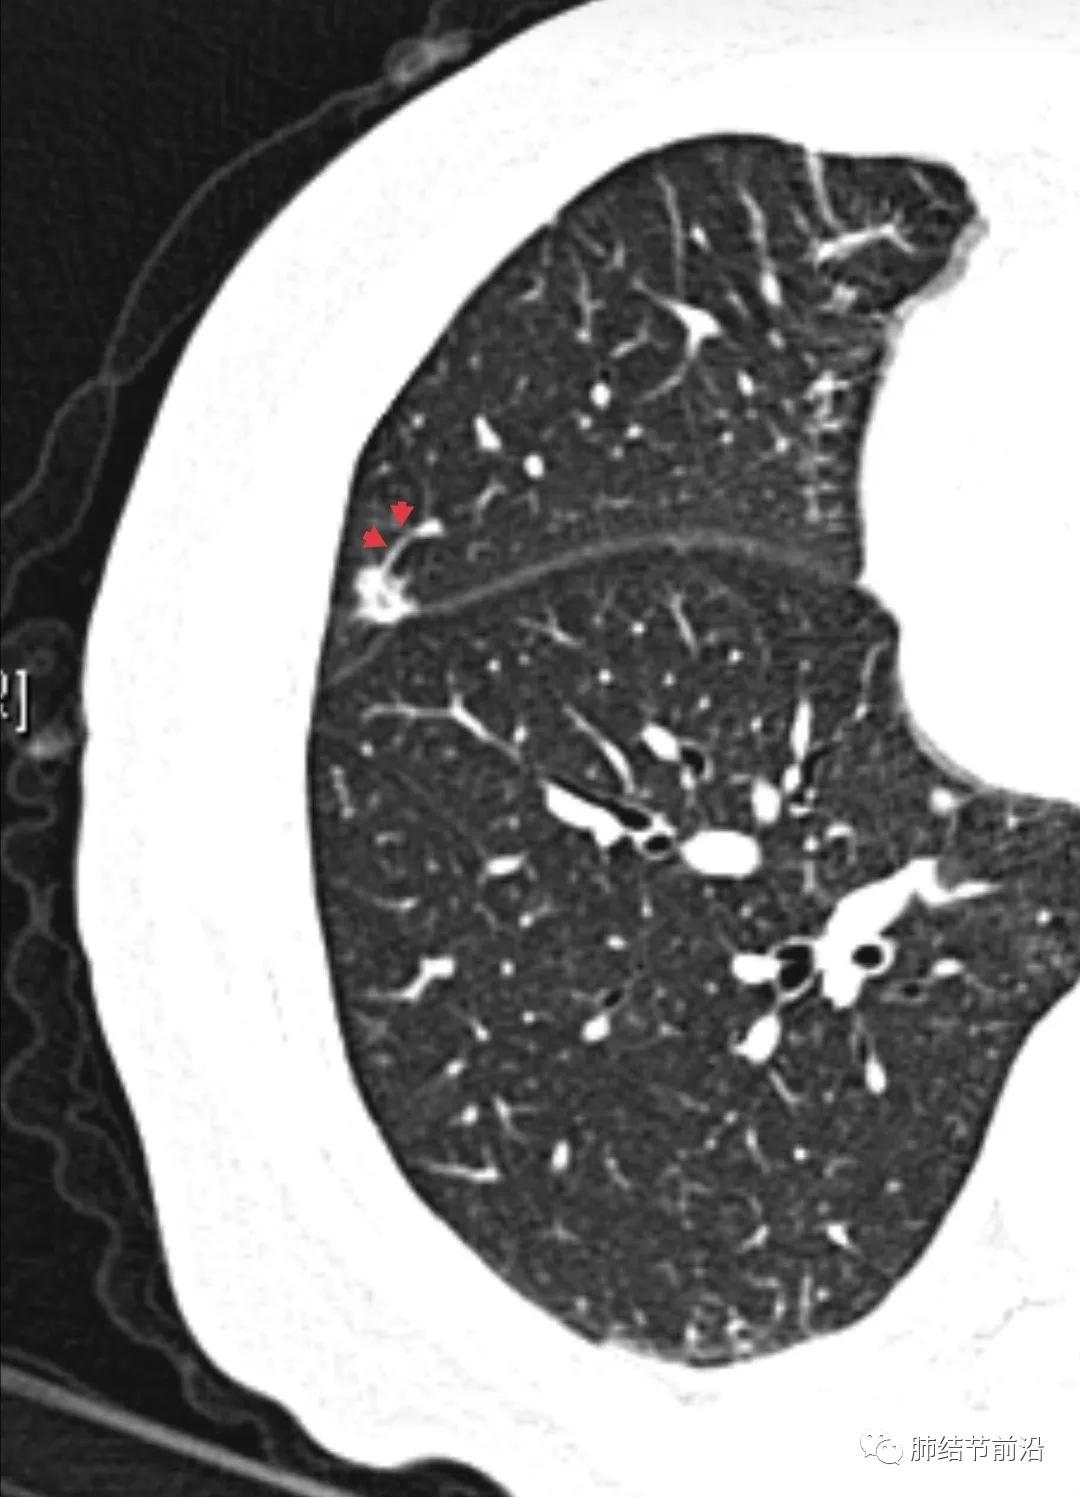

肿瘤组织需要氧供,新生血管是肿瘤的特征之一。传统的鉴别肺结节良恶性的标准之一就是血管集束征。然而在磨玻璃结节释放的血管生成因子并不强烈,新生血管不明显。则表现为诱导血管弯曲,出现明显有别于正常血管的弯曲现象,并向结节生长,称之为"血管弯"。这是肿瘤性磨玻璃/半实性结节很常见的特异性现象,出现这种表现,诊断磨玻璃/半实性结节为早期肺癌十拿九稳。“血管弯”名词引用自武汉市人民医院谭先华主任。

病例1:血管弯曲